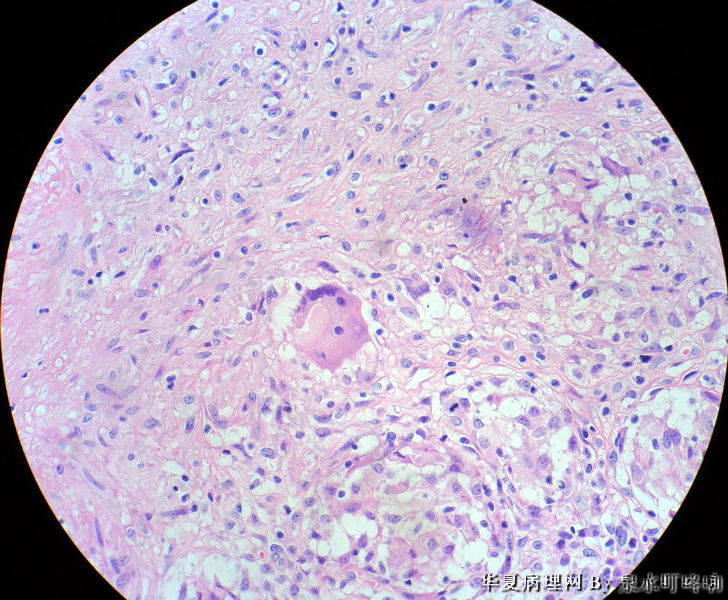

女,3岁,主因左腋窝肿物半年,术中见为肿大淋巴结,淋巴结内有脓液及坏死组织。

大体:灰红色组织一块,大小约4.6×3.5×2厘米,切面可见两个囊性区域,内容乳白色浓稠液体。